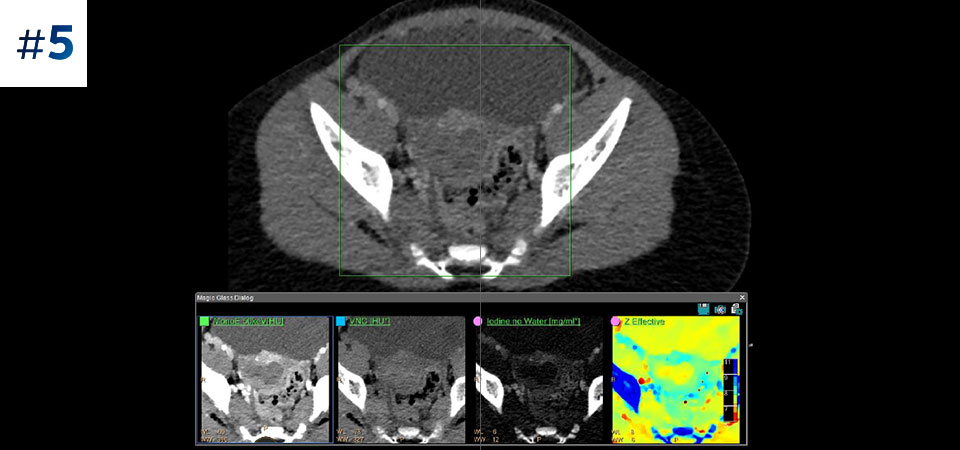

Zobacz różnicę pomiędzy tomografią komputerową opartą na detektorze spektralnym a konwencjonalną tomografią komputerową

Zobacz jak tomograf spektralny pomaga w diagnostyce pacjentów onkologicznych.

Nie ograniczaj się do konwencjonalnej tomografii komputerowej. Zobacz, jak wyniki uzyskane dzięki warstwom detektora spektralnego mogą zwiększyć pewność diagnostyczną.

Ograniczenie liczby ponownych badań Udoskonalona charakterystyka i wizualizacja tkanek może ograniczyć konieczność wykonywania ponownych badań, jaka zachodzi w przypadku badań o niezadowalającej jakości oraz przypadkowych obserwacji.